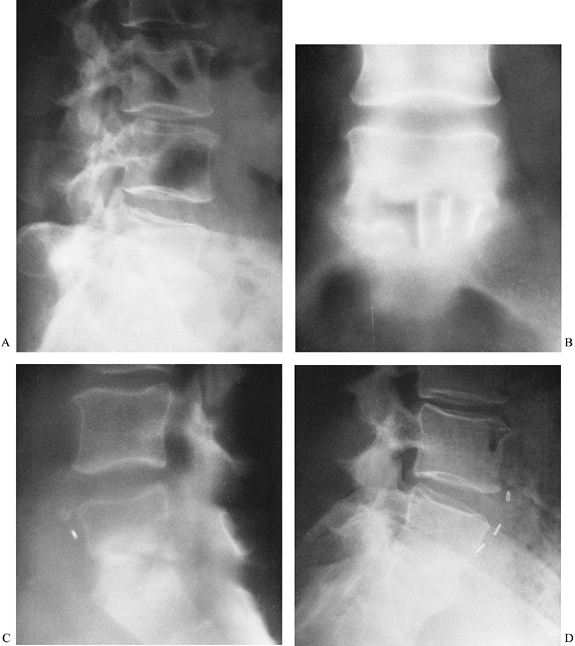

Figure 150.3. A,B:

This patient with osteomyelitis has complete loss of the disc space with partial destruction of the contiguous vertebral bodies. The lateral x-ray (B) shows kyphotic angulation of L-4 in relation to L-5. This 70-year-old woman was having severe pain and muscle spasm. The physical examination revealed loss of L-5 nerve root function on the right. C: The patient elected nonoperative care. After a needle biopsy revealed the causative organism, she was treated with antibiotics and a body jacket. At 4 months, a tomogram of the involved level shows osteophyte formation that is starting to bridge the disc space. D: A lateral x-ray taken at 4 months reveals correction of the kyphotic angulation. After 2 months of bed rest, a body jacket was applied and molded in hyperextension. E,F: Radiographs taken after 1 year show fusion of L-4 to L-5. She returned to work as a farm wife, pain free and with resolution of the foot drop due to the L-5 root lesion. This patient shows that nonoperative treatment can be successful. |

Disc-space narrowing is followed by endplate erosion, then by progressive vertebral body destruction (Fig. 150.3) (121).